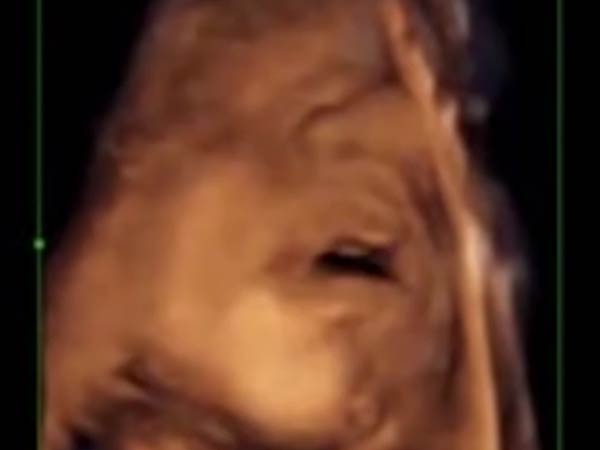

இதன்மூலம் 16 வார கருவிற்கு காது நன்றாக வளர்ச்சியடைந்து, கேட்கும் திறன் இருப்பதாக ஆய்வாளர்கள் கூறுகின்றனர். ஆனால், இதுவரை 18 வாரத்திலேயே சிசுவிற்கு காதுகேட்கும் எனக் கூறப்பட்டு வந்தது.

இந்த ஆய்வானது 14 வாரம் முதல் 39 வார கர்ப்பிணிகளைக் கொண்டு நடத்தப்பட்டது. சில சிறப்பு ஸ்பீக்கர்கள் மூலம் கர்ப்பத்தில் இருக்கும் குழந்தைகளுக்கு இசையைக் கேட்க வைத்து அவர்களின் ரியாக்ஷன்களை அல்ட்ரா சவுண்ட் மூலம் ஆய்வாளர்கள் கண்காணித்தனர்.

இந்த ஆய்வில் சாதாரணமாக இசையைக் கேட்டு 45 சதவீத சிசுக்கள் தலையையும், கால் மூட்டுக்களையும் அசைத்ததாகவும், 30 சதவீத சிசுக்கள் வாயை அசைத்து நாக்கை சுழற்றியதாகவும், 10 சதவீத சிசுக்கள் நாக்கை சுழற்றியதாகவும் ஆய்வாளர்கள் தெரிவித்துள்ளனர்.